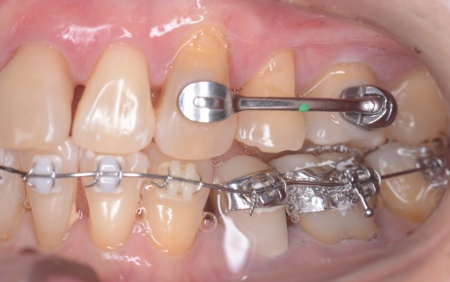

・ワイヤー矯正

歯の表面にブラケットと呼ばれるボタン状の装置を接着し、そこにワイヤーを通して歯を移動させる矯正治療です。

メリット:固定式の装置なので、歯をしっかりと移動させることができる

デメリット:自分では取り外せないため、歯磨きがしにくい

まずはワイヤー矯正を行い、ある程度まで歯並びを整えます。

その後アライナー矯正に移行し、正しい歯並びになるよう調整を行いました。